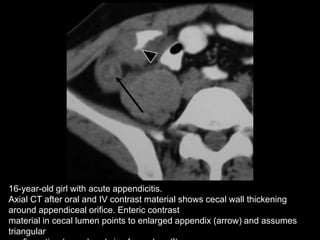

16-year-old girl with acute appendicitis.

Axial CT after oral and IV contrast material shows cecal wall thickening

around appendiceal orifice. Enteric contrast

material in cecal lumen points to enlarged appendix (arrow) and assumes

triangular